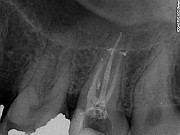

Polega na usunięciu zainfekowanej lub martwej tkanki z komory i kanałów zęba, dezynfekcji a następnie ich szczelnym wypełnieniu odpowiednim materiałem.

Leczenie zęba kanałowo jest trudne. Czasami może być długie i skomplikowane szczególnie, jeśli kanały są niedrożne lub już wypełnione albo w kanale tkwi złamane narzędzie. Leczenie może być przeprowadzone na jednej wizycie - dotyczy to z reguły zębów posiadających jeden kanał.